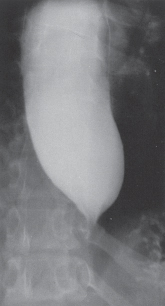

The pathogenesis of achalasia is presumed to be a neurogenic degeneration, which is either idiopathic or due to infection. In experimental animals, the disease has been reproduced by destruction of the nucleus ambiguus and the dorsal motor nucleus of the vagus nerve. In patients with the disease, degenerative changes have been shown in the vagus nerve and in the ganglia in the myenteric plexus of the esophagus itself. This degeneration results in hypertension of the LES, a failure of the sphincter to relax on swallowing, elevation of intraluminal esophageal pressure, esophageal dilatation, and a subsequent loss of progressive peristalsis in the body of the esophagus. The esophageal dilatation results from the combination of a nonrelaxing sphincter, which causes a functional retention of ingested material in the esophagus, and elevation of intraluminal pressure from repetitive pharyngeal air swallowing (Fig. 25-4). With time, the functional disorder results in anatomic alterations seen on radiographic studies, such as a dilated esophagus with a tapering, ‘bird’s beak’–like narrowing of the distal end (Fig. 25-5). (See Schwartz 9th ed., p 851.)

FIG. 25-5. Barium esophagogram showing a markedly dilated esophagus and characteristic “bird’s beak” in achalasia. (Reproduced with permission from Waters PF, DeMeester TR: Foregut motor disorders and their surgical management. Med Clin North Am 65:1244, 1981. Copyright © Elsevier.)